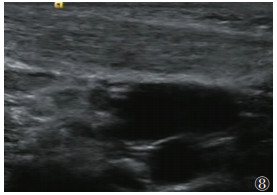

| 图 8 男,62 d,右侧CMT(非肿块型)声像图,右侧SCM厚约8.2 mm,肌纹理模糊,内回声增强 |

2.4